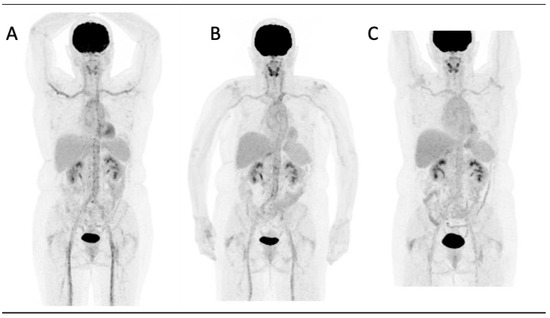

Figure 1 illustrates a case of GCA at the time of diagnosis and its subsequent post-therapy follow-up.

Figure 1.

A 66-year-old woman diagnosed with giant cell arteritis. (A) FDG-PET whole-body MIP image shows increased FDG uptake in the aorta, carotid, subclavian and iliac arteries. FDG uptake is higher than liver uptake (grade 3 according to the Meller scale) and thus categorized as pathologic. After treatment with tocilizumab and steroids a progressive improvement was observed transitioning from grade 2 (B) to grade 1 (C).